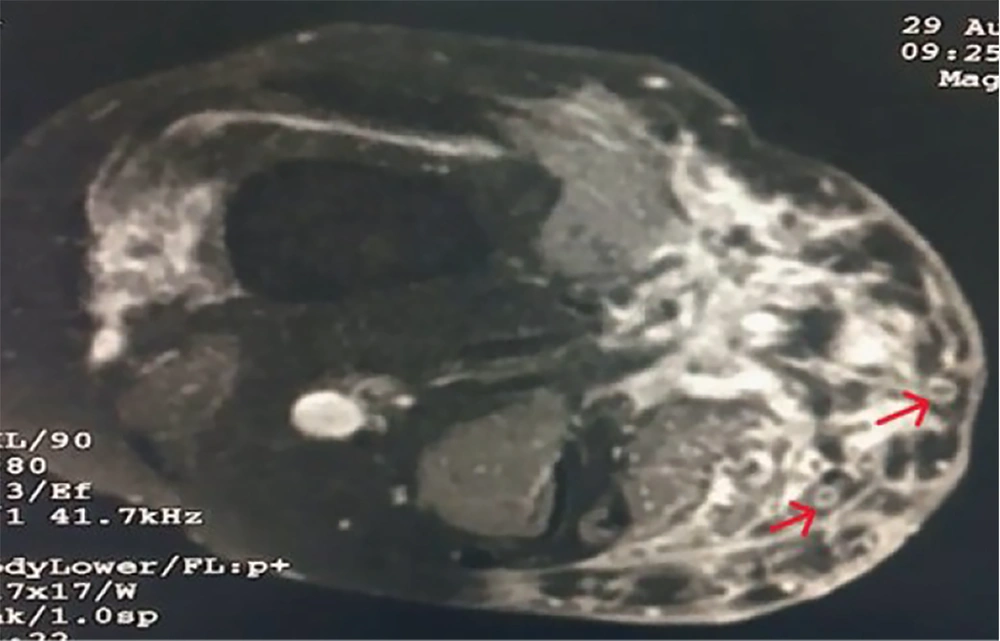

Radiological examination of the right knee included a local X-ray, which showed subcutaneous soft tissue swelling in the right knee joint region with heterogeneity, more pronounced on the medial aspect. Findings from the local ultrasound (USG) revealed multiple hypoechoic, interconnecting tracts, some of which were opening onto the skin. Diffuse subcutaneous thickening was noted involving the right knee joint. MRI (plain and contrast) was suggestive of heterogeneous altered signal intensity in areas involving the anteromedial aspect of the lower thigh, knee, and upper leg, with extensions and a peripheral hyperintense (circle) with a central hypointense area, known as the ‘Dot in circle sign’ (Figure 4).

Radiological examination revealed subcutaneous soft tissue with heterogeneity. Early bone involvement is more common in actinomycetoma compared to eumycetoma. Although MRI has high sensitivity for diagnosing mycetoma, with the ‘Dot in circle’ sign seen in both actinomycetoma and eumycetoma, it cannot identify the causative organism (13).